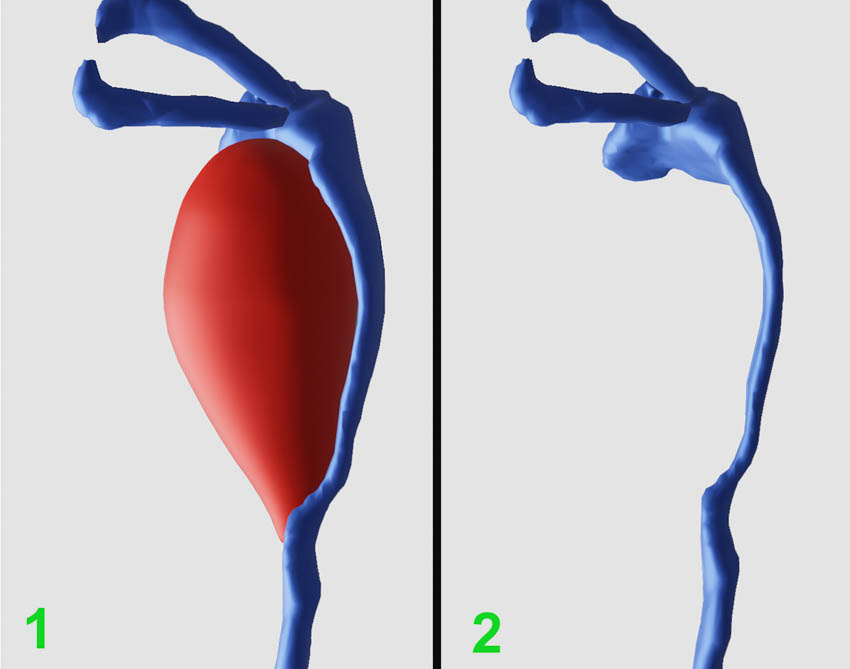

Medical Imaging XR (Medicalholodeck AG, Zurich, Switzerland) three-dimensional reconstructions obtained from CT-DCG DICOM files showed a well-defined lesion in the left lacrimal sac fossa, extending up to the beginning of the nasolacrimal canal (bony). The lacrimal sac appeared to be compressed against the posterior wall of the lacrimal fossa (Fig. 2-4).

The reconstructions showed the intricate relationship of the lesion with the compressed lacrimal system (Fig. 5). The surgical plan was a careful excision.

Figure 3. Medical Imaging XR reconstruction shows isolated contrast dye in the left lacrimal passages (red) and significantly compressed lacrimal sac

Figure 5. Three-dimensional reconstruction shows relationship of the lesion with the compressed lacrimal system (posterior-anterior view from the back of the left orbit; 1- lacrimal system in blue color, the cyst in red color; 2-isolated, compressed lacrimal system)